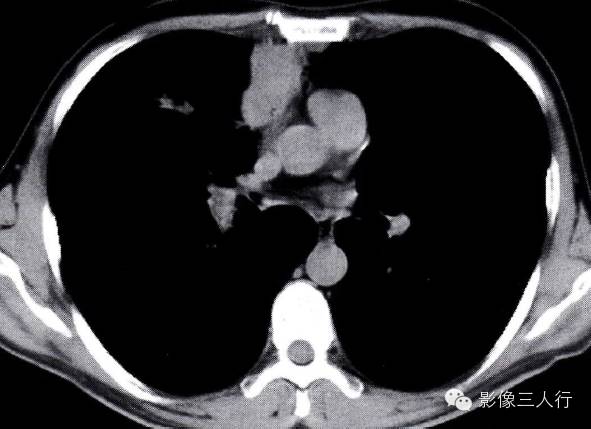

(1)纵隔旁肺脓肿中心低密度,边缘明显强化:靠近纵隔呈包块影,其内密度不均,中心多为相对较低密度,甚至表现为空洞。周围密度较高,并可有明显强化(图2-19)。

图2-19纵隔旁脓肿 左肺上叶前段纵隔旁脓肿,中心密度低,还有小点空洞形成